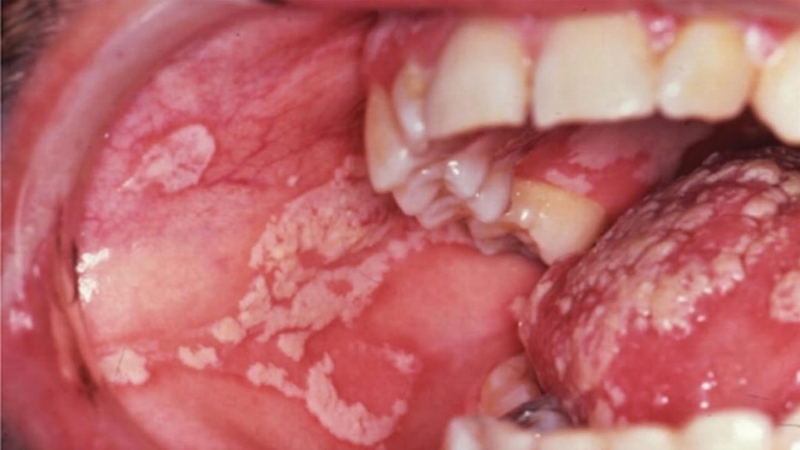

Nấm miệng hay tưa miệng là bệnh nhiễm trùng nấm men thuộc loài Candida. Bình thường loài nấm này tồn tại chủ yếu ở các bề mặt da một số nơi trong cơ thể như niêm mạc miệng, hầu họng, âm đạo… mà không gây hại cho cơ thể. Nhưng khi gặp yếu tố thuận lợi, loài nấm này phát triển vượt khỏi tầm kiểm soát gây nên bệnh nhiễm trùng nấm. Vậy nếu mắc phải bệnh nấm miệng bao lâu thì khỏi? Mời quý đọc giả theo dõi những chia sẻ sau đây từ các chuyên gia để biết câu trả lời.

Nấm miệng là tình trạng nấm Candia tăng sinh và gây bệnh ở khoang miệngNhững người có nguy cơ cao bị nhiễm nấm miệng nếu:

Giai đoạn đầu, bệnh nấm miệng có thể không có bất cứ triệu chứng nào. Nhưng khi tình trạng bệnh nặng hơn, người bệnh có thể có một hoặc một số các dấu hiệu và triệu chứng sau đây: